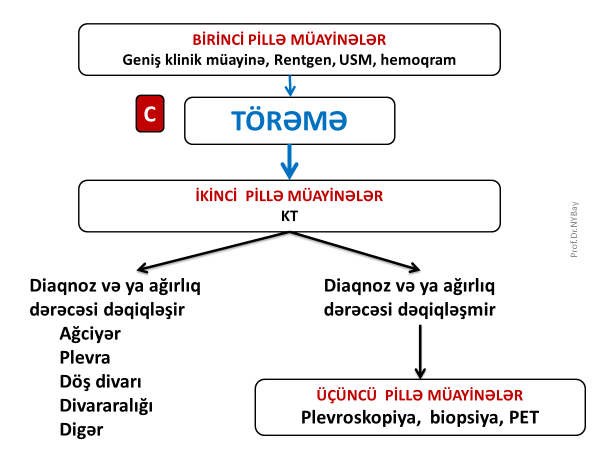

Plevrada kütlə

Ağciyərin periferik törəmələri, döş qəfəsi divarının, divar aralığının, diafraqmanın, diafraqmaaltı orqanların törəmələri rentgendə və USM-də plevra proyeksiyasında görünə bilər. USM periferik kütlələrin xarakterini, plevral dəyişiklikləri göstərə bilir, lakin bunun hansı orqana mənsub olduğunu dəqiqləşdirmək üçün adətən KT lazım gəlir.

Plevranın özünün birincili törəməsi kimi mezoteliomanı göstərmək olar ki, bu da nadir rast gəlinir. Ona görə də plevra proyeksiyasında törəmə tapıldıqda ilk növbədə digər orqanları axtarmaq gərəkir. Törəmə plevral mənşəli olarsa və təbiəti məlum olmursa əksər hallarda invaziv müayinələr (torakotomiya və ya plevroskopik biopsiya) edilir. Törəmə bədxassəli olduğu hallarda mərhələni təyin etmək üçün PET istifadə edilə bilər (Şəkil 4).

Şəkil 4. Plevral törəməyə diaqnostik yanaşma